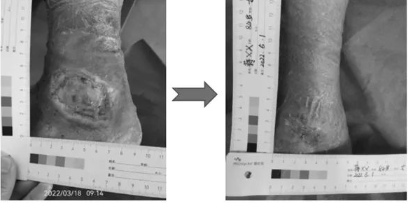

另一名静脉性溃疡的患者蒋某某,女,84岁,患左下肢静脉性溃疡一年余,多方寻医未果,住院治疗效果不佳,溃疡创面继续扩大,大量渗出,疼痛难忍,患者性情大变,情绪激动易怒,不愿与人交流。家人六神无主,其女儿经过朋友介绍,于2022年3月18日带老人到红河州第三人民医院造口伤口门诊就诊,门诊专科护士对患者关怀备至,舒缓患者激动情绪,用专业技术为患者进行专科护理,经过43天的精心护理,患者溃疡创面基本愈合,疼痛消除。患者及家属感激涕零。(文/图 许海燕)